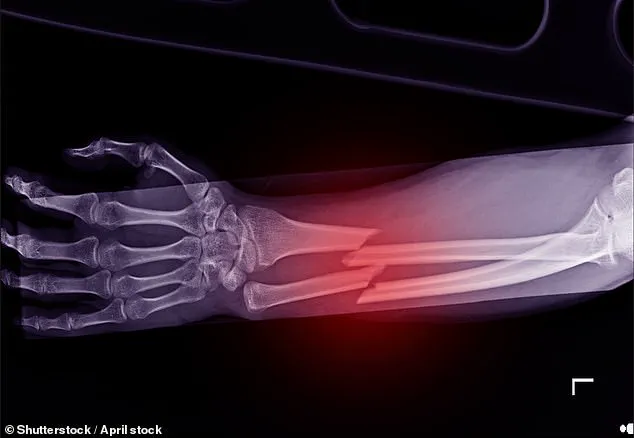

Osteoporosis, a condition that weakens bones and increases the risk of fractures, affects 3.5 million people in the UK.

Alarmingly, one in two women over 50 will break a bone due to the disease.

These medications can prevent life-threatening hip fractures—a critical concern given that more than a quarter of hip fracture patients die within a year, and one in ten dies within a month, according to the National Institute for Health and Clinical Excellence (NICE).